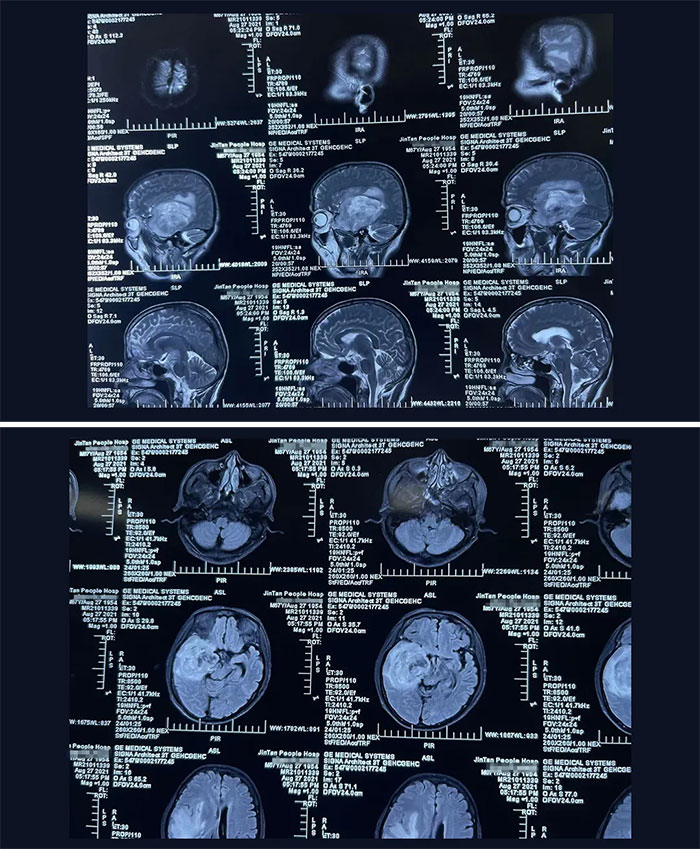

家住江蘇省某市的林先生(化名)今年68歲,從事業(yè)單位退休下來已經(jīng)八年了。今年7月,林先生被車撞了一下,當(dāng)時(shí)感到持續(xù)性頭痛,伴左側(cè)肢體乏力持續(xù)加重,在家人陪同下前往當(dāng)?shù)蒯t(yī)院就醫(yī)。因?yàn)槠綍r(shí)每年單位都會組織退休員工進(jìn)行體檢,除了頭部不做CT及核磁共振MRI外,其他身體部位都體檢到的,除頭部外身體各處無恙,F(xiàn)在這一查頭部,著實(shí)讓他及家人嚇了一大跳。林先生右側(cè)丘腦、基底節(jié)、顳葉占位病變,占位體積巨大,最大直徑約 8cm,呈浸潤性生長、邊界不清,周圍大片水腫帶;腦干、右側(cè)側(cè)腦室受壓變形,中線結(jié)構(gòu)受壓向左偏移11mm。考慮為腦惡性腫瘤,膠質(zhì)瘤可能性大。

▲ 丘腦占位病變體積巨大,且與腦組織邊界不清,壓迫腦干、大腦腳,若任其發(fā)展或危及生命

根據(jù)患者的病史、癥狀以及體征,再結(jié)合CT和磁共振(MRI)檢查,對病變部位以及惡性程度級別,有了初步的臨床判斷。“患者的腦腫瘤體積巨大,且位于腦部重要功能區(qū),已壓迫腦干,顱內(nèi)高壓所致神經(jīng)功能損害癥狀明顯,隨著病情加重,腦組織受壓位移程度更為嚴(yán)重,隨時(shí)可出現(xiàn)腦疝,需立即手術(shù)。”教授解釋道,腦疝是一種十分兇險(xiǎn)的臨床危重癥,發(fā)生速度快,極短時(shí)間內(nèi)就可能造成患者生命危險(xiǎn),病死率、致殘率極高,且預(yù)后不良。